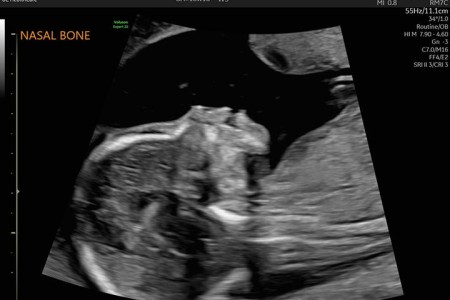

20-Week Ultrasound (Anatomy Scan)

Read More